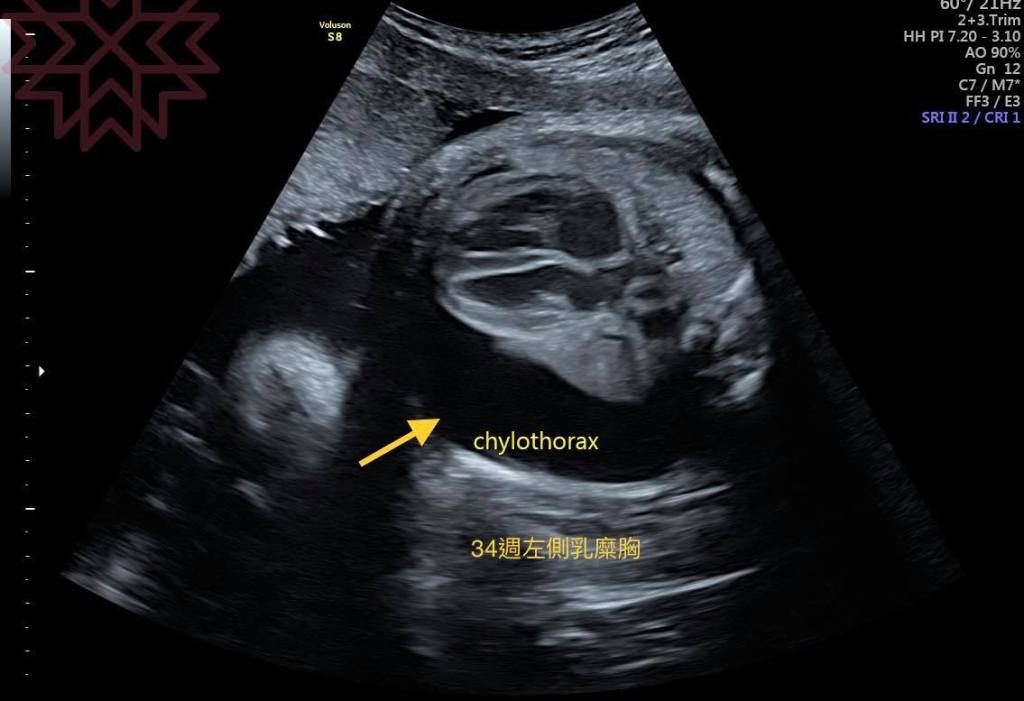

還記得這位媽咪來到我的門診是34週了

那時候在外院診斷單側乳麋胸

來到我門診想聽聽我的看法

在這個週數發現其實有點尷尬